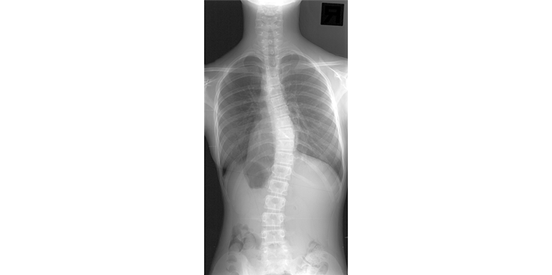

背骨を正面から見ると、背骨はまっすぐになっていますが、側弯症とは背骨がねじれを伴って横に曲がってしまう疾患です。

側弯症は、レントゲン検査によって診断され、背骨の弯曲の程度は図のように、「コブ角」という指標で表されます。「コブ角」とは、脊柱の上下で最も曲がりの強い椎体から直線を伸ばし、その 2本の直線の交差する角度のことを示します。

この「コブ角」が 10°以上の場合、「側弯症」と診断されます。